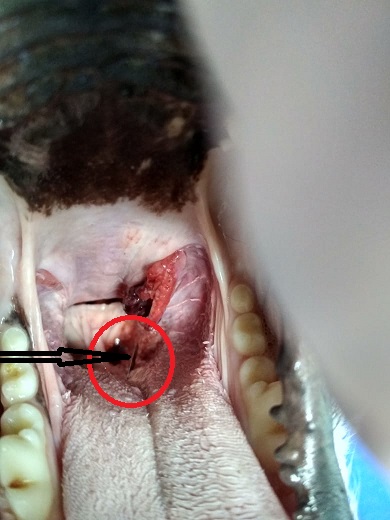

Владельцы обратились с жалобой на отказ от твердой пищи, мягкую ел неохотно и с затруднениями. Не давал открыть пасть, испытывал болезненность при пальпации. Животному проведена общая анестезия, осуществлен осмотр каудальных отделов ротовой полости. Обнаружено инородное тело – швейная игла, расположенная продольно в толще языка.

Свободный конец иглы (с ушком) выступал над поверхностью корня языка и сильно травмировал, буквально изрезал, слизистую оболочку и подлежащие мягкие ткани в области небной миндалины.

Владельцы обратились с жалобой на отказ от твердой пищи, мягкую ел неохотно и с затруднениями. Не давал открыть пасть, испытывал болезненность при пальпации. Животному проведена общая анестезия, осуществлен осмотр каудальных отделов ротовой полости. Обнаружено инородное тело – швейная игла, расположенная продольно в толще языка.

Свободный конец иглы (с ушком) выступал над поверхностью корня языка и сильно травмировал, буквально изрезал, слизистую оболочку и подлежащие мягкие ткани в области небной миндалины.